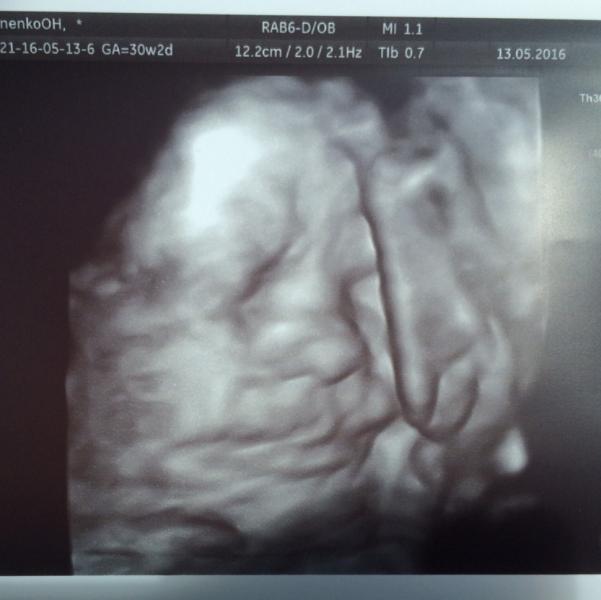

Сегодня были на узи у #Ковальчук . Не зря ему оды воспевают, весь день на эмоциях сидим с мужем обсуждаем😊 встреча с малышом прошла успешно ❤️!

Клево !)) у нас на фотке прям портрет , мы прям видем какой он , ну на стока реальное ) тоже все любуемся )))

видно, что бруталити)) какой нибудь, Георгий, Александр или Федор😎